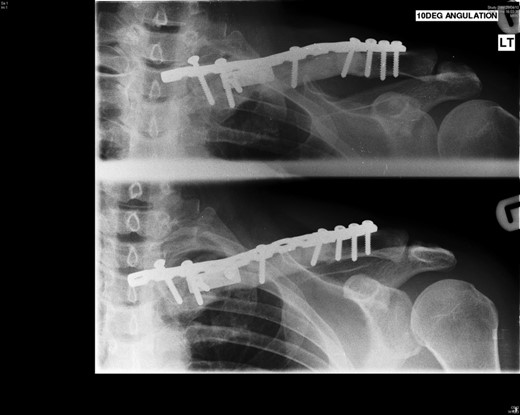

Four years following the procedure, after discomfort in her shoulder, X-rays revealed that the plate had broken and there was a fracture of the clavicle. This plate was subsequently removed and an underlying non-union was found, but no evidence of recurrence of the tumour. She has been managed symptomatically since and has a full range of shoulder movements but some discomfort when doing heavy lifting, which she therefore avoids (Figs 5 and 6).